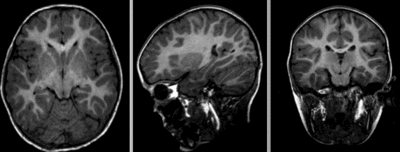

Registration Results

unregistered

original unregistered

rigid

affine

affine registered nonrigid registered (5,5,5 BSpline unmasked)

BSpline (7x7x7) unmasked

visualization of the nonrigid deformation component only